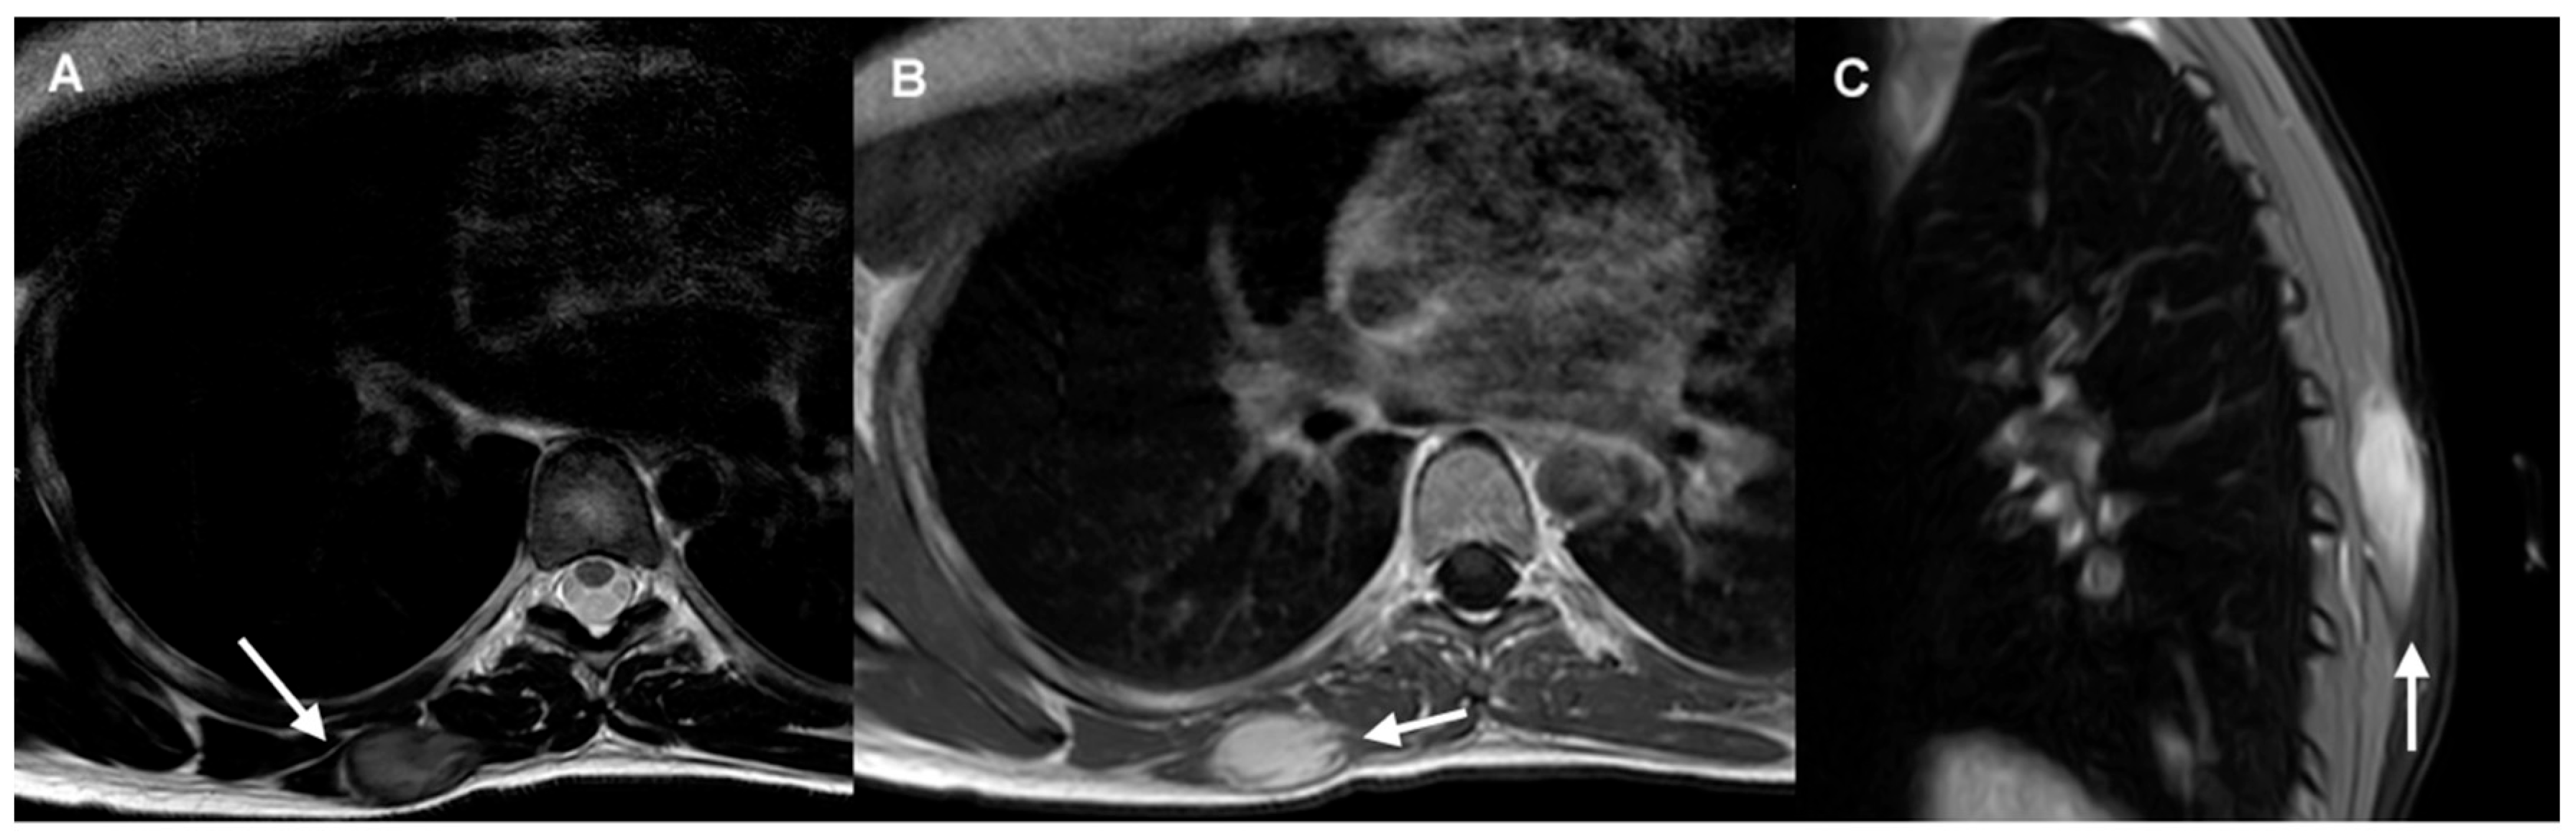

- CT and MRI are the imaging modalities of choice for treatment planning, image-guided procedures, and follow-up in patients with DTs (IV, B).

- MRI is considered the optimal imaging modality for evaluating extra-abdominal DTs (IV, B).

- CT is preferred in the follow-up of intra-abdominal DTs, particularly for evaluating the extent of disease and identifying potential complications (IV, B).